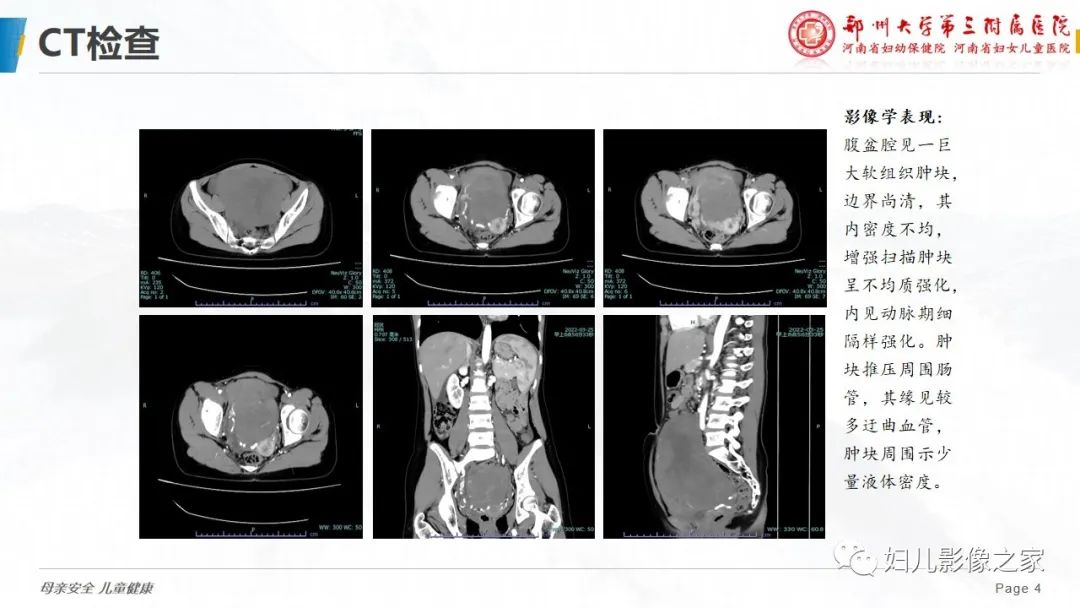

【病例】卵巢无性细胞瘤1例CT及MR影像-3